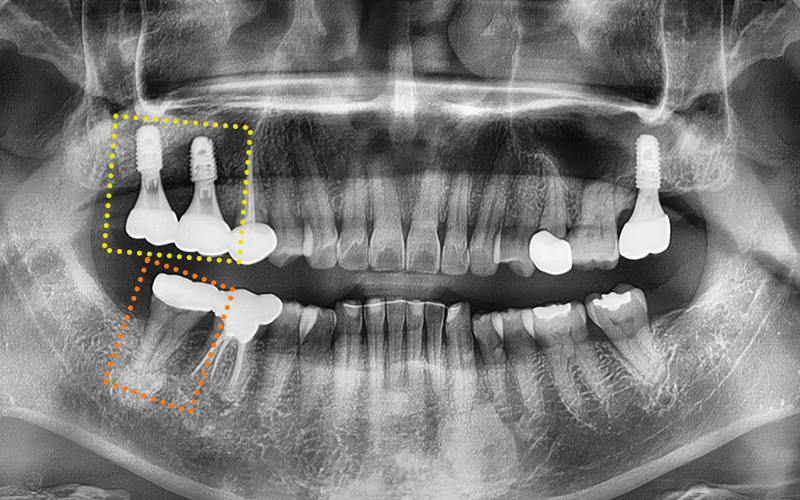

✅ Before > After

2024.11.22

▼ ▼ ▼

2025.04.15

✅ Prosthetic restoration completed after treatment!

The prosthetic work has been completed precisely,

with careful consideration of the occlusion!